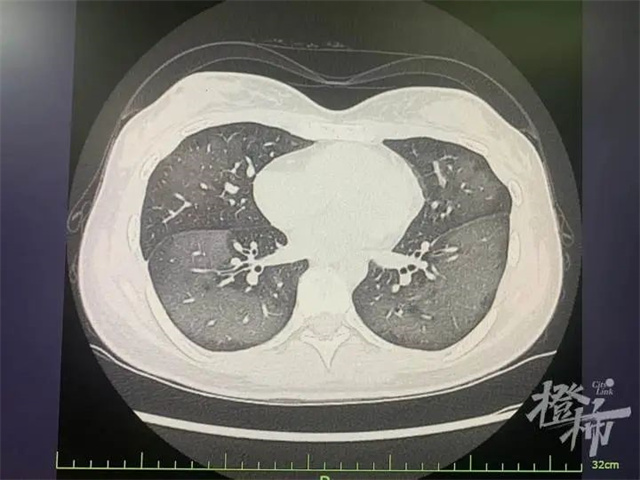

一个小时过去 她感觉越来越不舒服 呼吸越来越困难 于是前来就医 经过CT检查发现 丽丽的双肺呈现 大范围白色样病变 报告提示“白肺” 丽丽被诊断为“急性过敏性肺炎”,急诊专家对丽丽给予吸氧、激素抗炎抗过敏等对症支持处理后,急性症状得到缓解,她被收入呼吸内科病房进一步住院治疗。